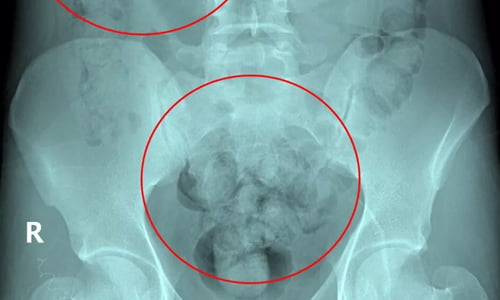

Şüpheli tavırları dikkat çeken B.E.O.’nun midesinde uyuşturucu olabileceği ihtimali üzerine hastaneye götürüldü. Götürüldüğü hastanede yapılan incelemede B.E.O.’nun sindirim sisteminde 96 kapsül içinde 1 kilo 844 gram kokain tespit edildi.